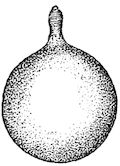

Fig. 3.—Pig suffering from osseous cachexia (fourth stage).

114. The fourth phase, or period of osteomalacia, i.e. softening of the bones, is also the last. It is rarely seen in large animals like horses and oxen, because accidents so often accompany the preceding stages and necessitate slaughter; but it is common in goats and pigs.

In this phase the bones become elastic, soft and depressible, yielding to the pressure of the operator’s fingers.

Fig. 4.—Deformity of the face in the horse shown in Fig. 2.

The flat bones are particularly liable to this change, which is common to domesticated animals. The bones of the head are the first to suffer; later those of the pelvis. The lower jaw becomes swollen, particularly about the centre of the branches which may attain three, four, or five times, their normal thickness.

The depression in the submaxillary space disappears. The upper jaw undergoes similar changes, becoming deformed and thickened until the cavities of the sinuses and the hollow appearance of the palate are lost, while the face is so changed that it cannot be recognised as that of a horse, goat, etc.

The molar teeth are almost buried, their tables alone being visible at the bottom of a depression, the edges of which rise above the neighbouring parts (pig).

Mastication is clearly impossible, the jaws appear paralysed, the muscles powerless, and only swallowing is possible, a fact which explains why life is only prolonged to this stage in animals which can be fed with a spoon or bottle (pigs and goats). The bones of the cranium, although greatly changed in texture, are always less deformed than those of the face.

The changes are such that it is often easy with a mere post-mortem knife to cut the head completely in two. Osseous tissue, properly so-called, has disappeared.

Fig. 5.—Head of a pig suffering from osseous cachexia.